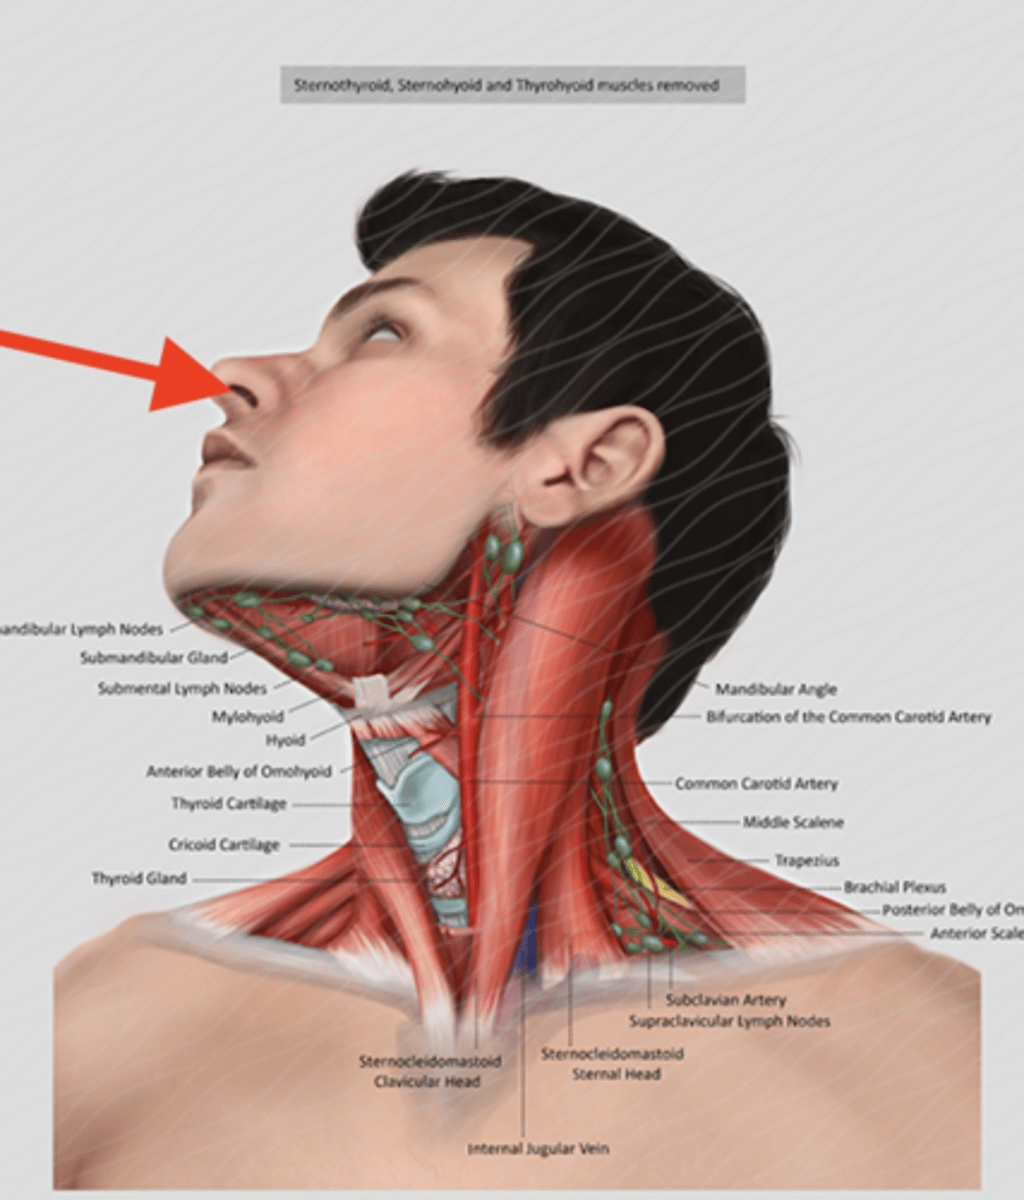

anterior scalene

middle scalene

posterior scalene

sternocleidomastoid